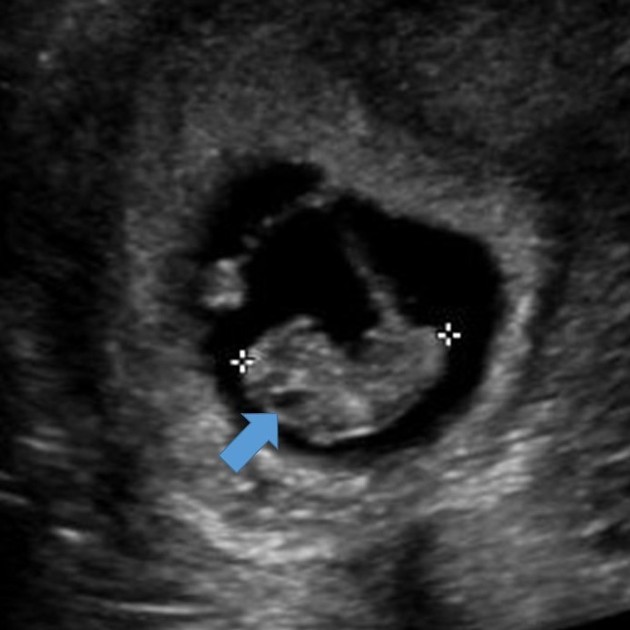

What are we seeing in this image?

Rhombencephalon